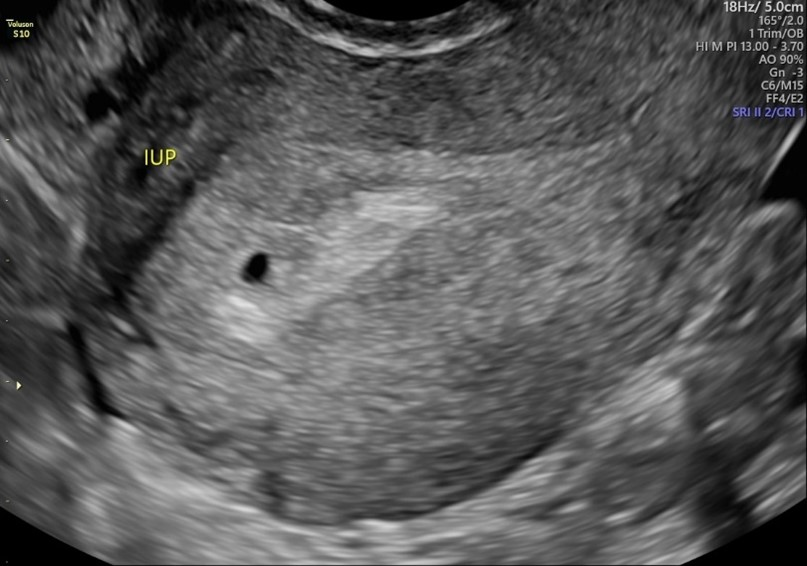

산과력 0-0-0-0, 29세 여성이 무월경 5주에 질 출혈로 내원하였다. 혈압은 118/68 mmHg, 맥박은 88회/분, 호흡은 20회/분, 체온은 36.7℃로 측정되었다. 골반진찰 시 소량의 혈액이 고여 있으나 자궁 경부는 닫혀 있고 추가적인 출혈은 없었다. 소변 임신 검사 결과 양성이며, 환자의 혈액형은 Rh(-)으로 확인되었다. 질 초음파 검사 결과이다. 필요한 처치는 무엇인가?

Imp: 절박유산 (threatened abortion)

• 본 증례는 자궁출혈이 있었지만 active bleeding은 아니며, 자궁경부가 닫혀있으므로 threatened abortion에 준하여 보아야 하며, 따라서 RhIG를 투여한다.